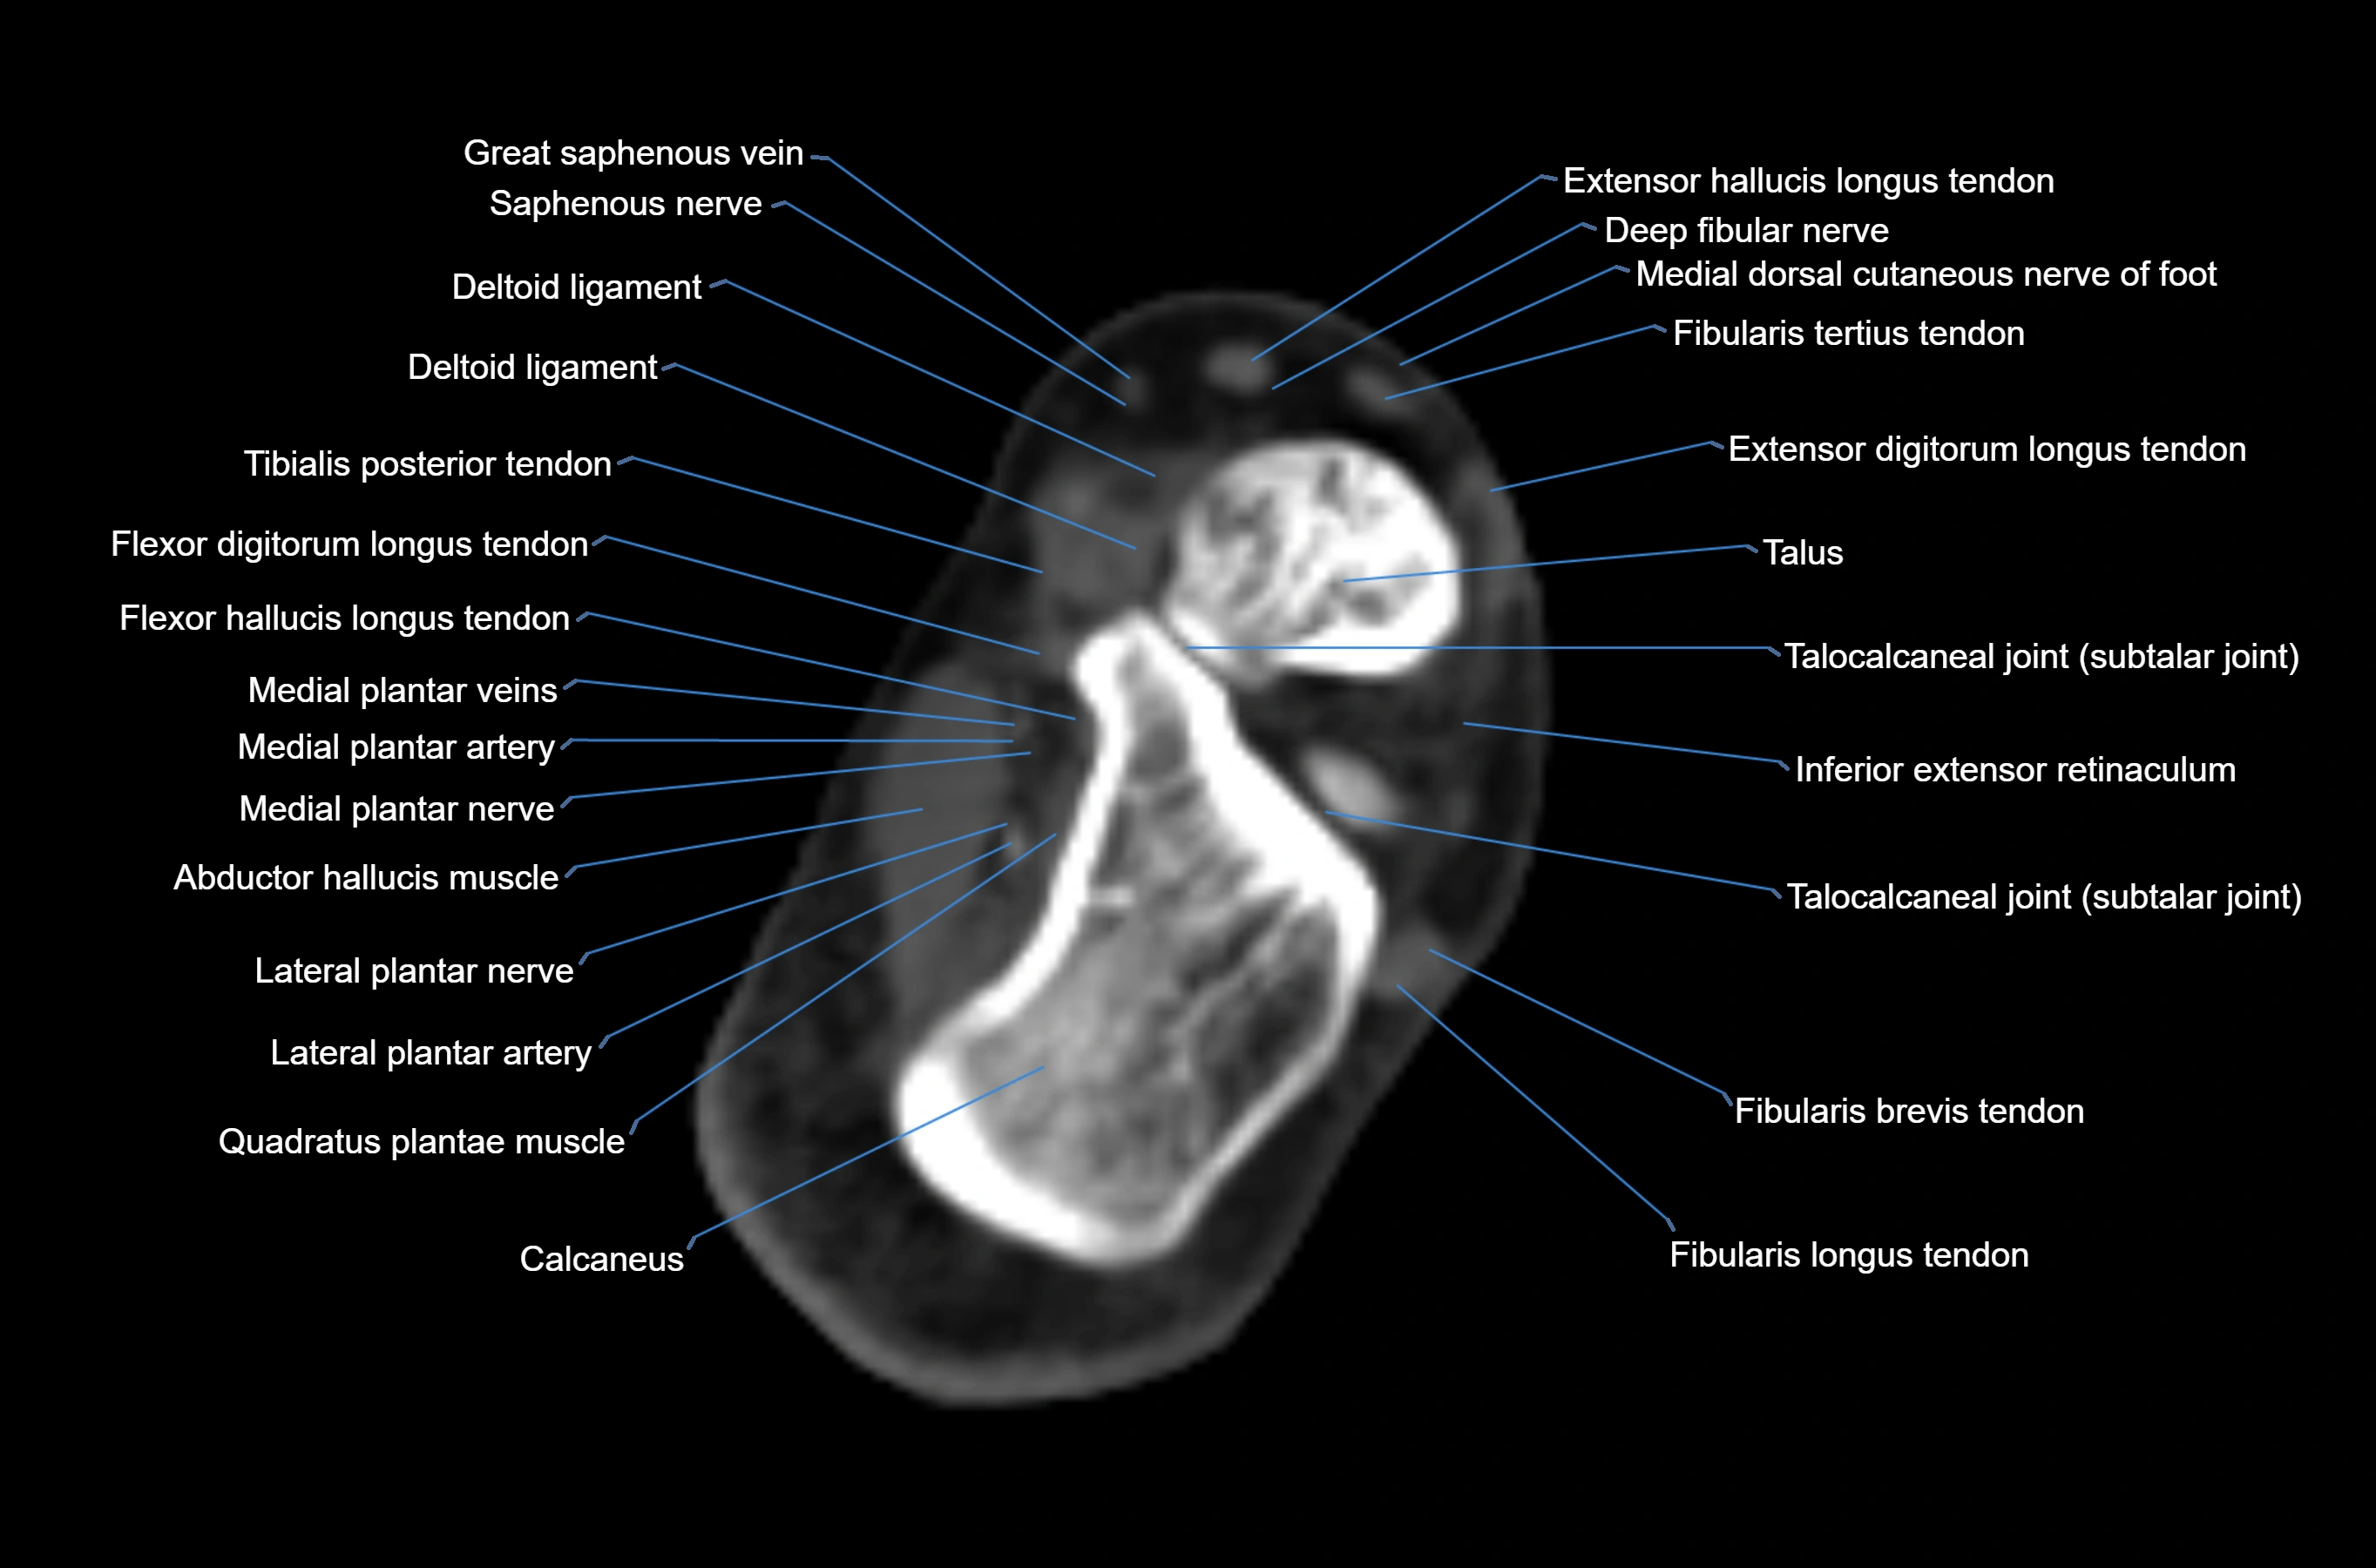

CT image